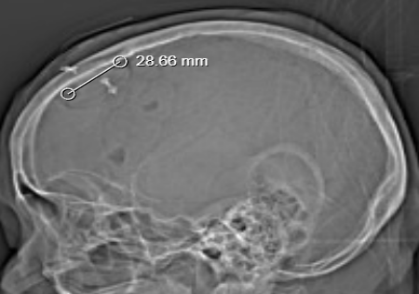

1.神经内镜手术创伤更小。以基底节区脑出血为例,传统的额颞部问号形切口,其长度至少要达到15cm 以上,切开颅骨大小约为8×10cm。而神经内镜手术切口长度仅需3 - 5cm,切开颅骨直径大小约 3cm,创伤明显更小。

在神经内镜治疗脑内血肿手术中,手术通道一般建立在额中回,而额中回前部为相对功能哑区,通道方向与纤维束方向平行。这种顺纤维束的手术操作,减少了手术带来的神经功能副损伤,术后患者的恢复情况相较于传统手术更好。对于大量出血患者,在传统手术过程中,为追求最大程度的颅内减压,往往会去除颅骨骨瓣,待患者术后恢复平稳后,还需要进行再次手术进行颅骨缺损的修补。而神经内镜手术不需要去除颅骨骨瓣,避免了术后二期颅骨修补手术,降低了患者的经济负担。